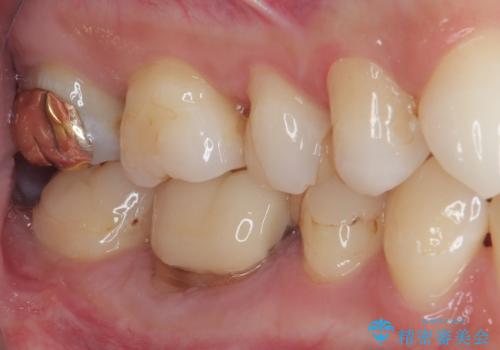

右下奥歯は既に根管治療が行われており、セラミッククラウンが装着されていました。

セラミッククラウンを壊して再度根管治療を行い、その後セラミッククラウンを装着する方法か、外科的に歯根の先端を切除し、炎症の原因である細菌を取り除き治癒を図る方法とを提案し、極力クラウンを壊さずに治療を進めたいとの希望により、歯根端切除術を行うこととしました。